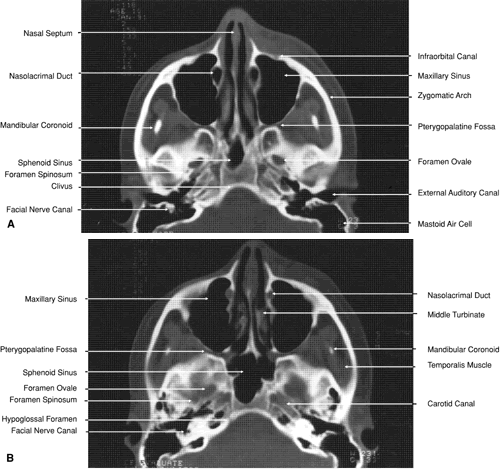

The globe is shown in Figure 12. The orbit and periorbital structures are shown in Figures 13 through 16, and the optic canal is shown in Figures 17 through 26. The cavernous sinus and optic chiasm are shown in Figures 27 and 28, and the posterior visual pathway and cranial nerves are shown in Figures 29 through 33.

Fig. 29. A. Axial computed tomography soft tissue image at the level of the base of skull. B. Axial computed tomography bone window image at the level of the base of skull.

The inferior orbital fissure is associated with several important soft tissue and bony structures. The maxillary division of the trigeminal nerve enters the fissure through the foremen rotundum and pterygopalatine fossa, dividing into the infraorbital and zygomatic nerves (see Figs. 20 and 21). This latter nerve separates into the zygomaticofacial and zygomaticotemporal nerves entering the zygomatic bone of the lateral orbital wall through small canals before exiting onto the face. The pterygopalatine fossa is bounded anteriorly by the pterygoid process of the sphenoid bone, the greater wing of the sphenoid, the maxilla, and the palatine bone (see Figs. 21 and 29). In addition to the maxillary division of the trigeminal nerve, it contains the pterygopalatine ganglion and its sensory, parasympathetic, and sympathetic branches and a portion of the maxillary artery. It communicates with the orbit by way of the inferior orbital fissure, the nasal cavity through the sphenopalatine foremen, and with the infratemporal fossa by way of the pterygomaxillary fissure. In addition to the foremen rotundum, sphenopalatine foremen, and pterygomaxillary fissure, the pterygoid and pharyngeal canals also enter into the fossa (see Fig. 29). After leaving the pterygopalatine fossa, the infraorbital nerve travels in the inferior orbital fissure a short distance before turning directly anteriorly into the infraorbital groove and canal within the maxillary bone. Finally it exits from the anterior surface of the bone 4 to 6 mm inferior to the midportion of the inferior orbital rim (see Fig. 19). The infraorbital artery, a terminal branch of the internal maxillary artery, accompanies the nerve along most of its course. Other branches of the maxillary division of the trigeminal nerve include branches to the pterygopalatine ganglion and the posterior, medial, and anterior superior alveolar nerves, which supply sensation to the upper teeth and gums.